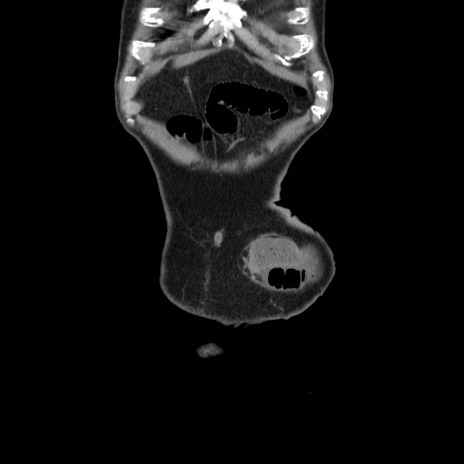

症例24(冠状断像)

【症例】80歳代男性

【主訴】左側腹部痛、嘔吐

【現病歴】本日早朝より左腹部に痛みあり。昼頃嘔吐認めたため、救急要請。

【既往歴】直腸癌(Mile手術)、胆摘

【身体所見】意識清明、BT 35.9℃、BP 221/93mmHg、SpO2 97%(RA) 、腹部:左ストーマ周囲に限局性の腹部膨隆あり。 膨隆部自発痛・圧痛あり・軟。

【データ】WBC 7700、CRP 0.09